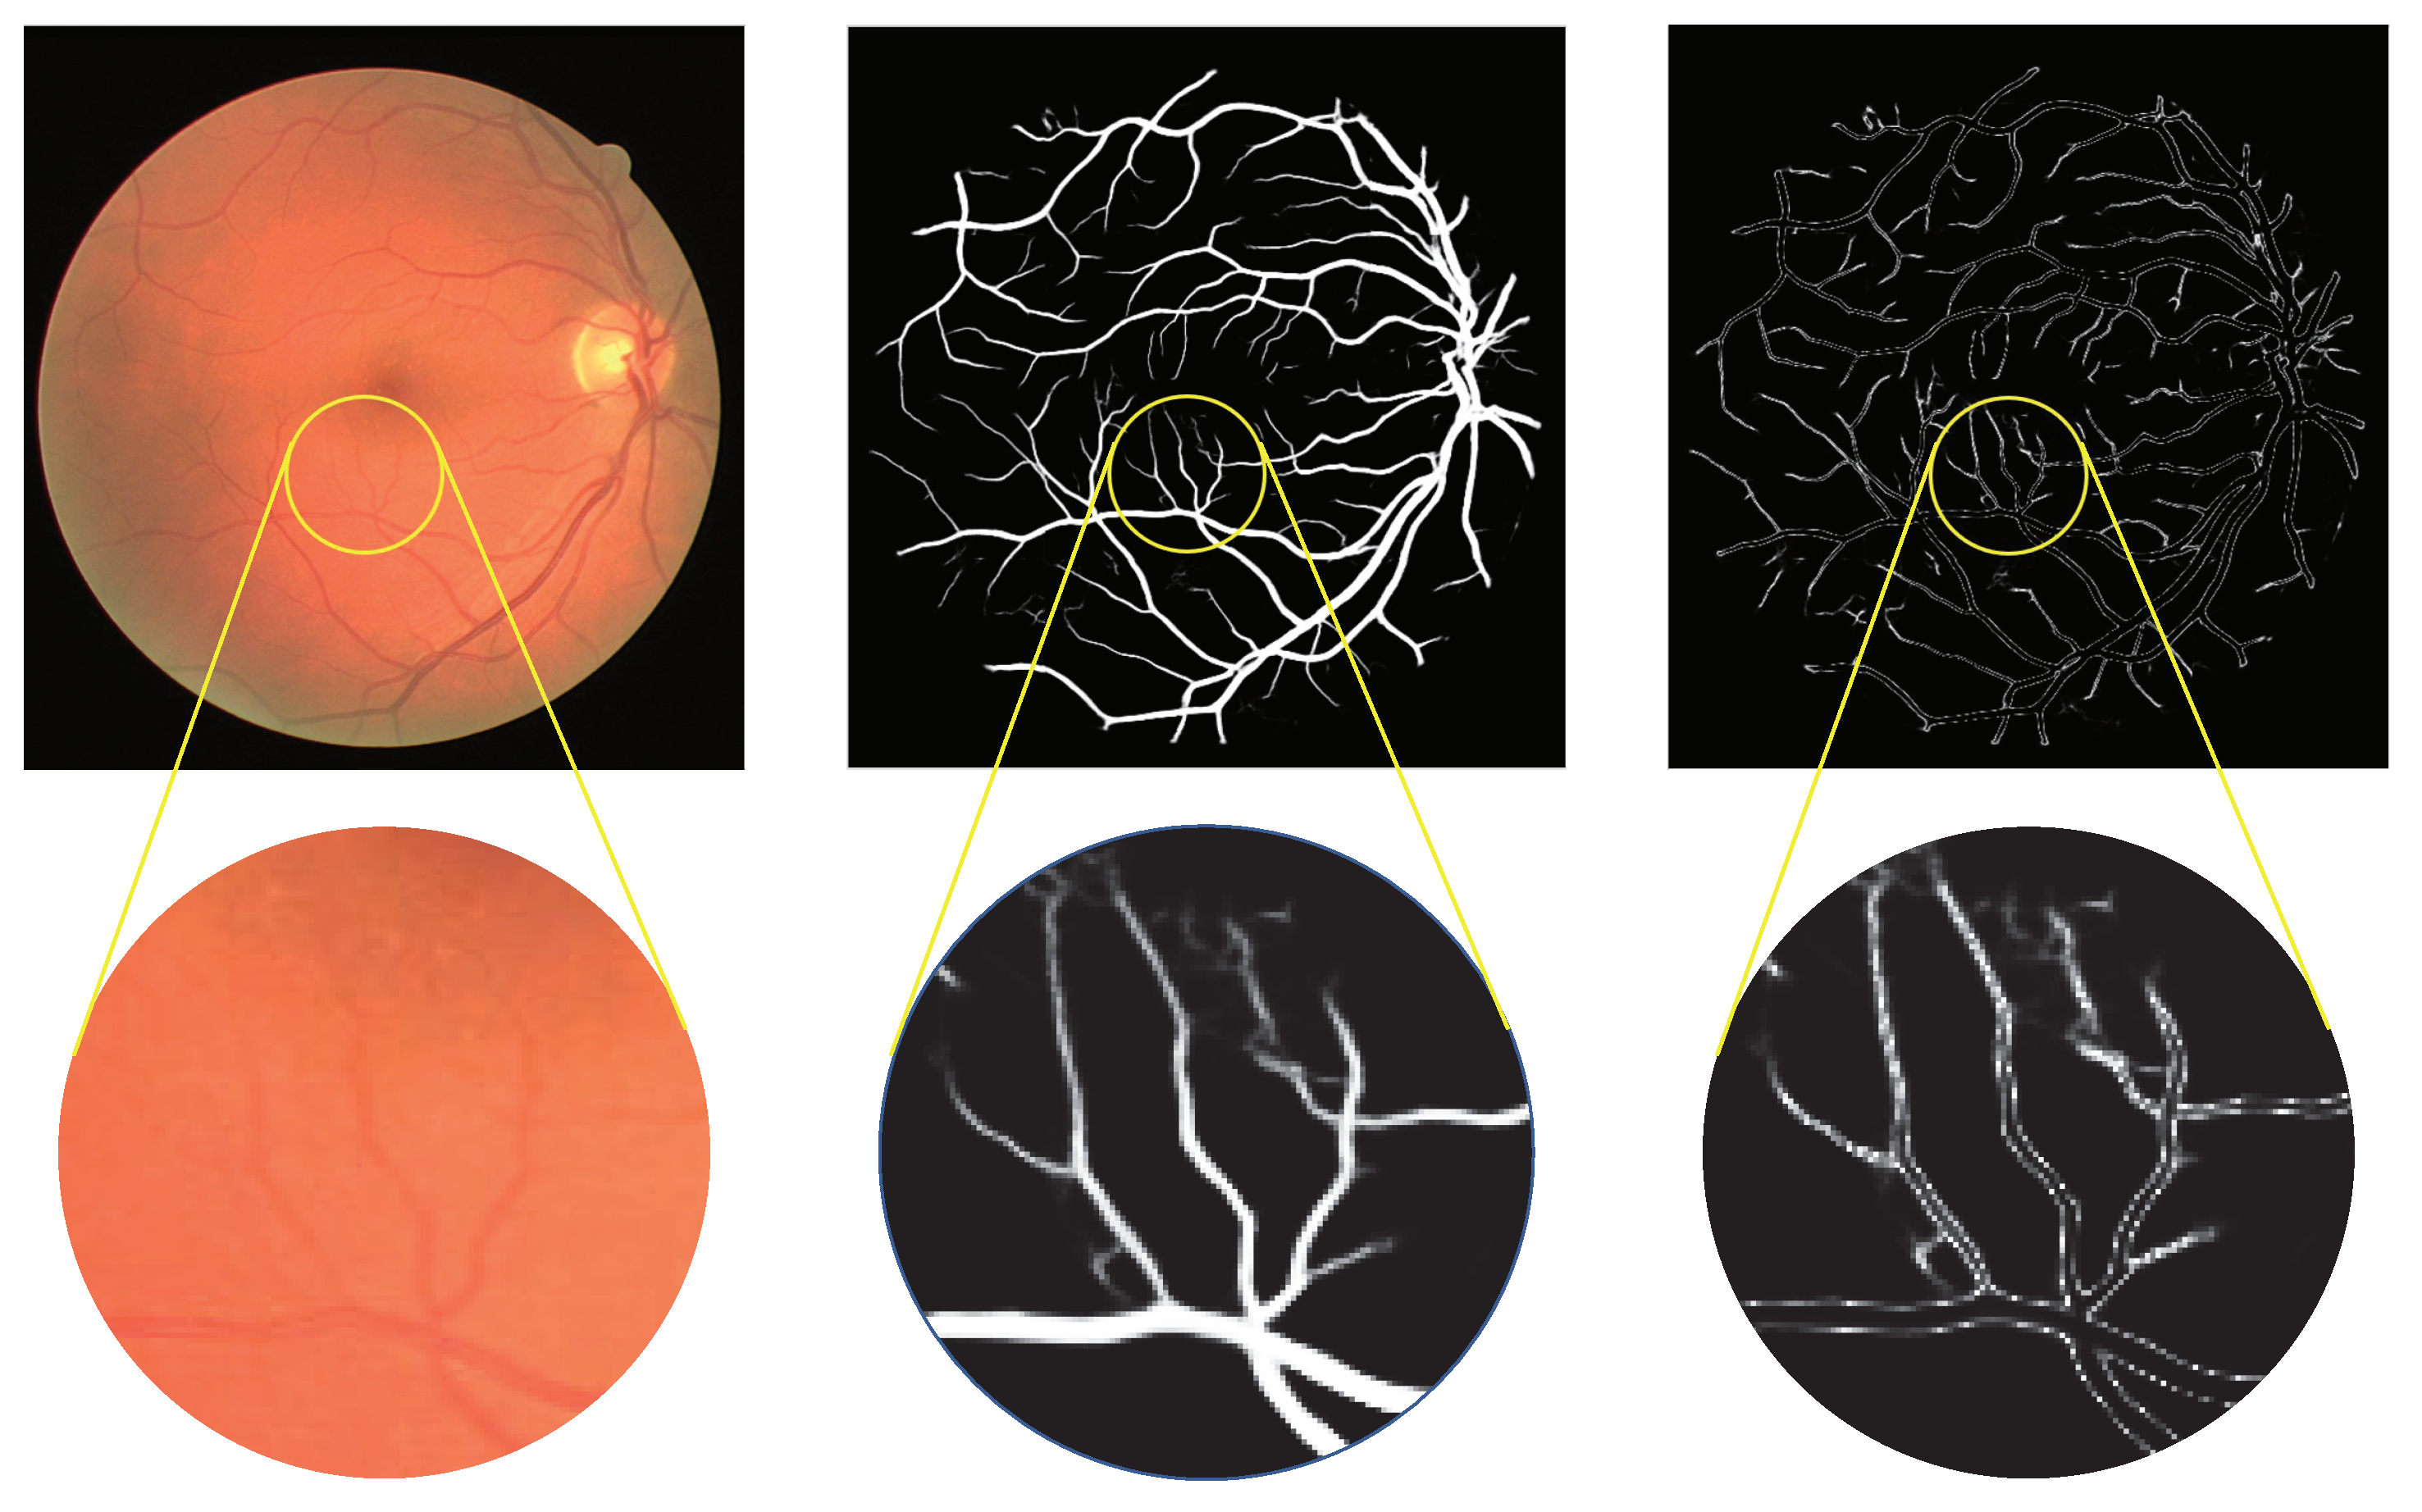

After processing by this activation function, the pixels of the capillary vessel pixels and vascular boundaries, with a probability close to 0.5 in the feature maps [5], are improved to 1 e 0.5 , and the pixels of the background and thick vessel declined to 0. Figure 5 shows the results produced by the activation function. As illustrated in the enlargement window, the pixels representing the capillaries and the edges of the thick vessel are maintained. Through utilizing the enhanced micro-vessel feature map to improve A/V classification, the impact caused by the imperfect vessel segmentation is alleviated.

Figure 5. Schematic diagram of the effect of MFI module on vascular feature enhancement. The left subfigure shows the original image, and the middle portrays the output of the MVE module. The right subfigure displays the enhanced blood vessels after applying the MFI module, which enhances the details and edges of the vascular features.